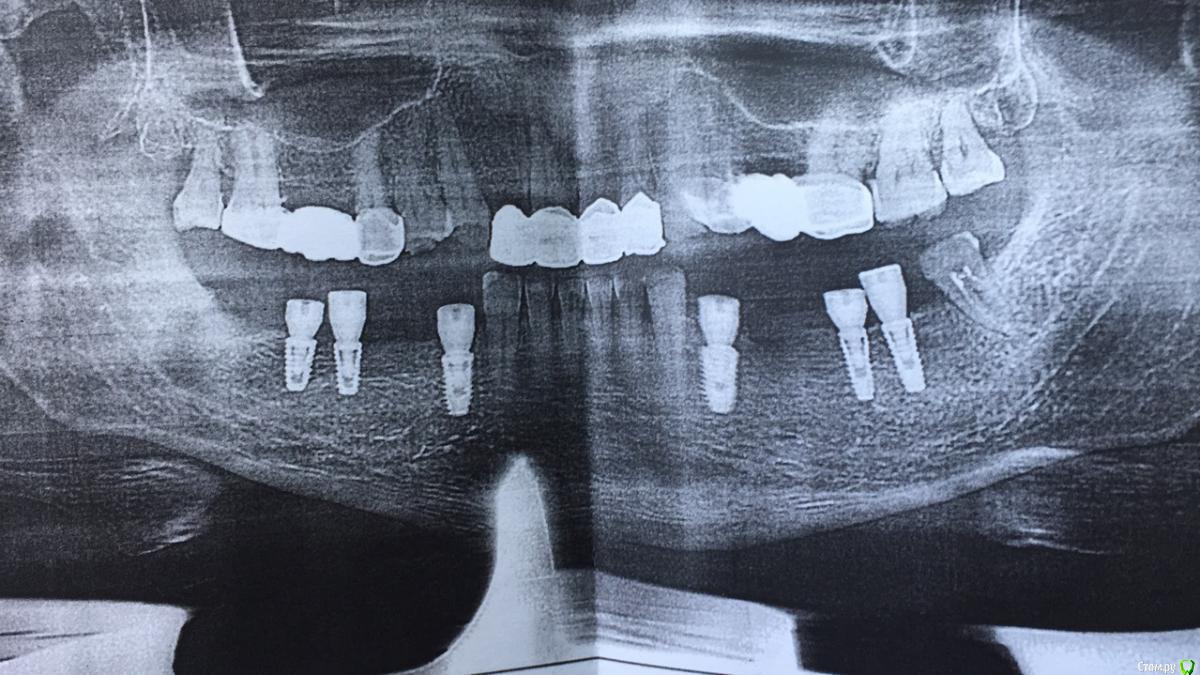

Foxtrot Опубликовано 28 августа, 2018 Автор Поделиться Опубликовано 28 августа, 2018 Здравствуйте! Просто захотелось отписаться по данному клиническому случаю. Удалил, почистил, установил импланты + формики. Десну не успел, скорее всего сделаю в еще один этап. (зуб 3.8 пока оставил) Ссылка на комментарий

Дмитрий Л. Опубликовано 28 августа, 2018 Поделиться Опубликовано 28 августа, 2018 Спасибо за кейс.Почему вы установили в позициях премоляров суб-, а моляров - эпикрестально? На чём держится прикус? Ссылка на комментарий

Foxtrot Опубликовано 29 августа, 2018 Автор Поделиться Опубликовано 29 августа, 2018 Спасибо за вопрос. В области 34,44 было проведено удаление с одномоментной установкой имплантов, этим обусловлено такое их заглубление. Я думаю в результате дальнейшего ремоделирования кости все будет ок. На данный момент прикус держится на оставшихся зубах. Ссылка на комментарий

Foxtrot Опубликовано 29 августа, 2018 Автор Поделиться Опубликовано 29 августа, 2018 Foxtrot, Вы хирург? Кто занимался планированием конструкции?Да, хирург. Планированием конструкции занимался ортопед. Но и с себя ответственности не снимаю) Такое позиционирование обусловлено ограничением по времени и по количеству визитов (пациент из другого города), а также оценкой потребностей пациента.Можете подсказать какие именно трудности предстоят в дальнейшей ортопедической части? Ссылка на комментарий